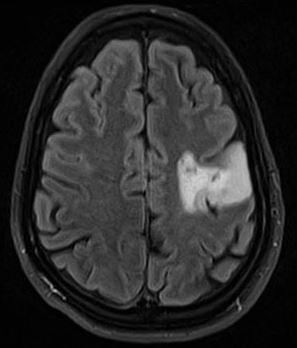

Brain Tumor is hard to detect and can go unnoticed sometimes during initial stage. That is why we decided to build a CNN (Convoluted Neural Network) and train it with images to enable detection of the tumor.

The CNN is trained with many tumor positive and tumor negtive results. By leveraging tensorflow, the deep learning library in python, we were able to successfully train the model to predict if a MRI scan, a test_dataset , has tumor or not with an accuracy range of 85-95%.

Scientists have found in a recent study that only three different genetic alterations drive the early development of malignant glioblastomas. At least one of these three cancer drivers was present in all tumors investigated. The tumors develop for up to seven years before they become noticeable as symptoms and are diagnosed. However, in contrast to their early development, glioblastomas, which return after therapy, share no concurrent genetic alterations. Abstract This review recounts the history of brain tumor diagnosis from antiquity to the present and, indirectly, the history of neuroradiology. Imaging of the brain has from the beginning held an enormous interest because of the inherent difficulty of this endeavor due to the presence of the skull. Because of this, most techniques when newly developed have always been used in neuroradiology and, although some have proved to be inappropriate for this purpose, many were easily incorporated into the specialty. The first major advance in modern neuroimaging was contrast agent–enhanced computed tomography, which permitted accurate anatomic localization of brain tumors and, by virtue of contrast enhancement, malignant ones. The most important advances in neuroimaging occurred with the development of magnetic resonance imaging and diffusion-weighted sequences that allowed an indirect estimation of tumor cellularity; this was further refined by the development of perfusion and permeability mapping. From its beginnings with indirect and purely anatomic imaging techniques, neuroradiology now uses a combination of anatomic and physiologic techniques that will play a critical role in biologic tumor imaging and radiologic genomics.